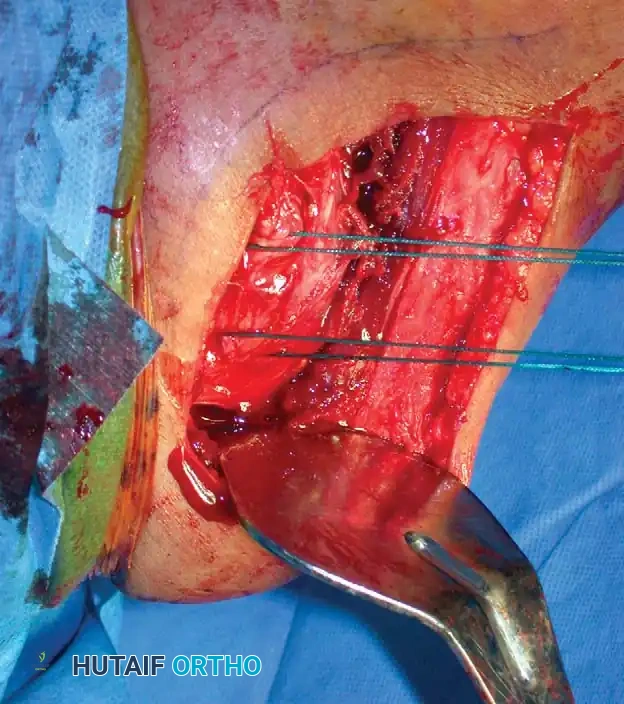

Open Reduction and Internal Fixation (Locked Plating)

For complex three- and four-part fractures, particularly in patients with osteoporotic bone, proximal humeral locking plates have revolutionized treatment. These fixed-angle constructs provide superior biomechanical stability compared to conventional non-locking plates.

Surgical Approach:

* The deltopectoral approach is the workhorse for proximal humeral ORIF, utilizing the internervous plane between the deltoid (axillary nerve) and pectoralis major (medial/lateral pectoral nerves).

* The cephalic vein is identified and typically retracted laterally with the deltoid to protect its tributaries.

Fixation Principles:

* Anatomic reduction of the medial calcar hinge is critical to prevent varus collapse.

* Heavy nonabsorbable sutures are passed through the rotator cuff tendons and tied to the plate to neutralize tuberosity pull.

* Locking screws are placed into the humeral head, ensuring they do not penetrate the articular surface (subchondral placement is ideal).